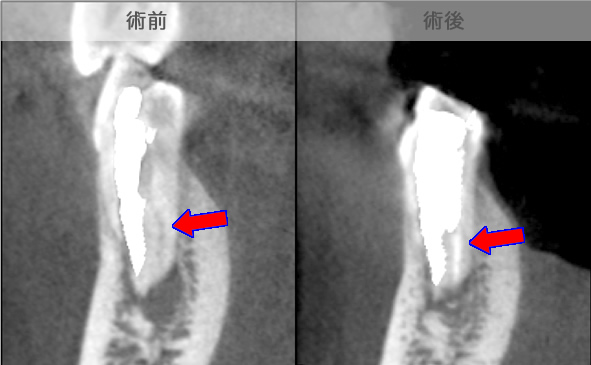

頬側骨壁の根尖部まで無くなっています。

MTA根充後11ヶ月で透過像が消失し、根尖部が正常化しました。

頬側骨の喪失が見られましたが17ヶ月で回復しました。

頬側骨の回復が確認できます。

| 治療説明 | 左下第一小臼歯の頬側根尖部からの排膿、痛みはないそうです。X線画像では根尖部に透過像を認められます。 頬側の骨も失われており、歯髄が死んだことが原因と考えられます。修復物を除去後根管治療を行い、根管充填後、透過像は消失、頬側骨も再生されていました。 |